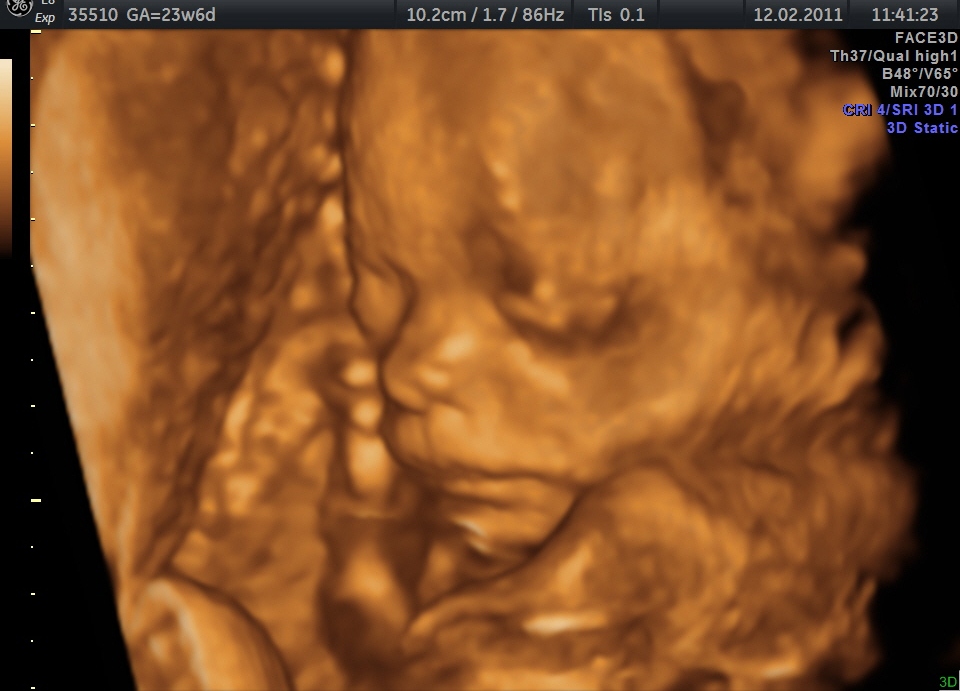

das erste Bild…

…es gibt nix mehr zu sagen…nur schauen…das goldkind…